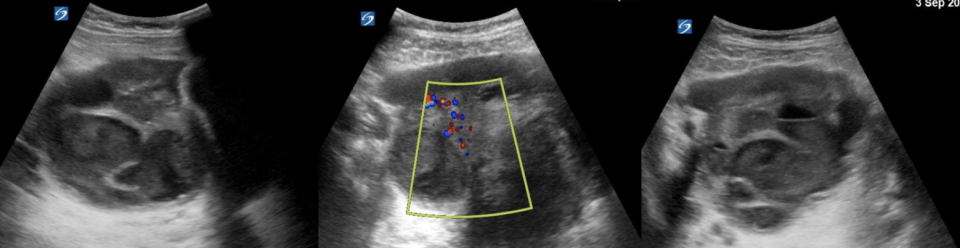

How Will I Know if I am Looking at an Ovary?

Appearance:

- The normal ovary will appear as an oval structure with an isoechoic, if not slightly hypoechoic stroma (the supportive connective tissue surrounding the follicles) and variable anechoic cystic follicles.

Location:

- The ovaries will appear just lateral to the uterus and medial to internal iliac vessels (Schwimer, 1985).

Hemorrhagic Cyst

PoCUS features

-

Reticular or “lacy” pattern of fine internal echoes (“fishnet” or “cobweb” appearance) — due to fibrin strands from clotted blood

Fluid–fluid levels (from settling of blood products)

May show retracting clot: fibrin components contract, causing a concave, sharp, curvilinear or triangular internal mass that pulls away from the cyst wall

Usually no internal Doppler flow (but circumferential wall flow may be seen)